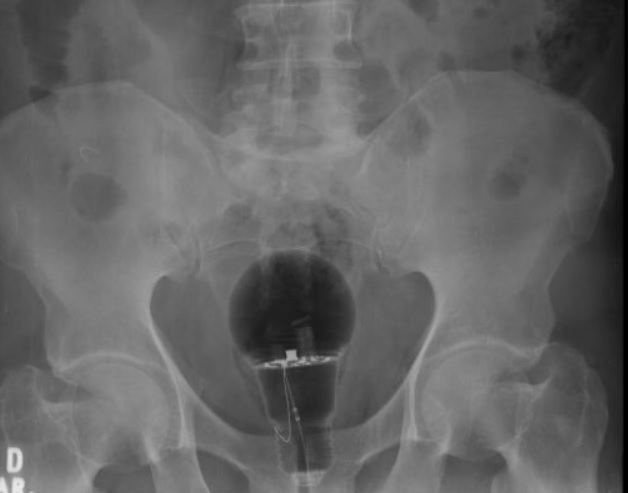

MUNDO – O médico Julian Pylori viralizou no Twitter após revelar que precisou da ajuda de dois colegas para retirar uma lâmpada do ânus de um paciente.

De acordo com o médico a sorte do paciente é que o objeto era de plástico. Se fosse de vidro teria estourado e poderia ter matado o paciente de hemorragia interna.